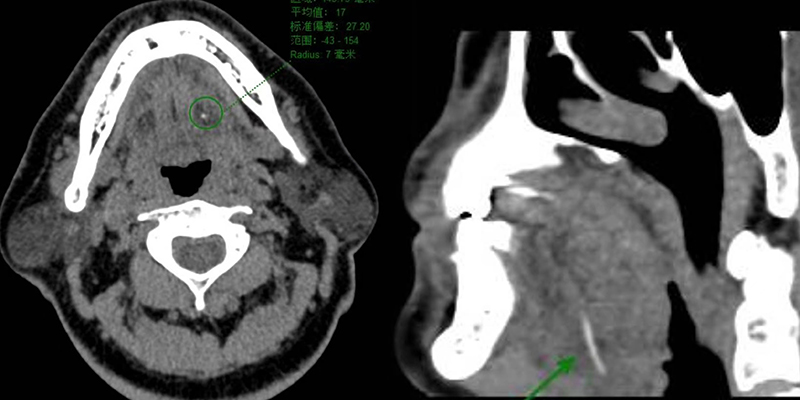

通過問診、專科查體及口咽部CT檢查,口腔科團隊很快為李先生明確了診斷,并定位魚刺已經穿透口底粘膜,沒入舌下肌肉深部,相應部位口咽腔腫脹變窄。

▲術前口咽部CT(魚刺位于綠色指示區)